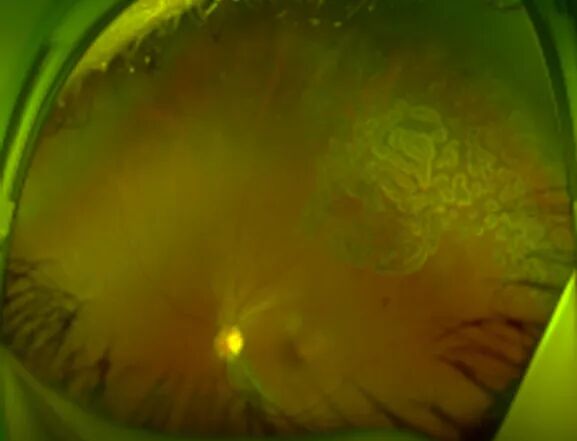

一名29岁的女性,以“左眼视力下降8天”就诊。3年前确诊SLE,并且自述右眼自幼视力差,在对其进行眼部体查时发现,其右眼视力为0.02,左眼为0.4,双眼前节均透明。下面这张图片是其眼底照相的表现,可以看到右眼视网膜血管走行清,左眼黄斑下方积血平面,黄斑未见新生血管,通过荧光血管造影显示颞侧周边视网膜可见新生血管膜伴出血。

一名21岁的年轻女性,以“双眼视力下降3月余”为主诉就诊,此前已经确诊了SLE ,并且口服激素1年。但其在3月余前无明显诱因出现双眼视力急剧下降,就诊当地医院诊断为“双眼脉络膜炎”,在予药物治疗后无明显好转故就诊于我院。在对其进行眼部体查时可见其右眼裸眼视力为0.25,左眼为0.15,右眼最佳矫正视力为0.8,左眼为0.3。眼底检查双眼视网膜面见大量斑片样脉络膜病灶,自发荧光显示“黑心白边”,病灶围绕视盘,眼底荧光造影显示病灶处有荧光着染,脉络膜造影病灶显示相对应处低荧光。